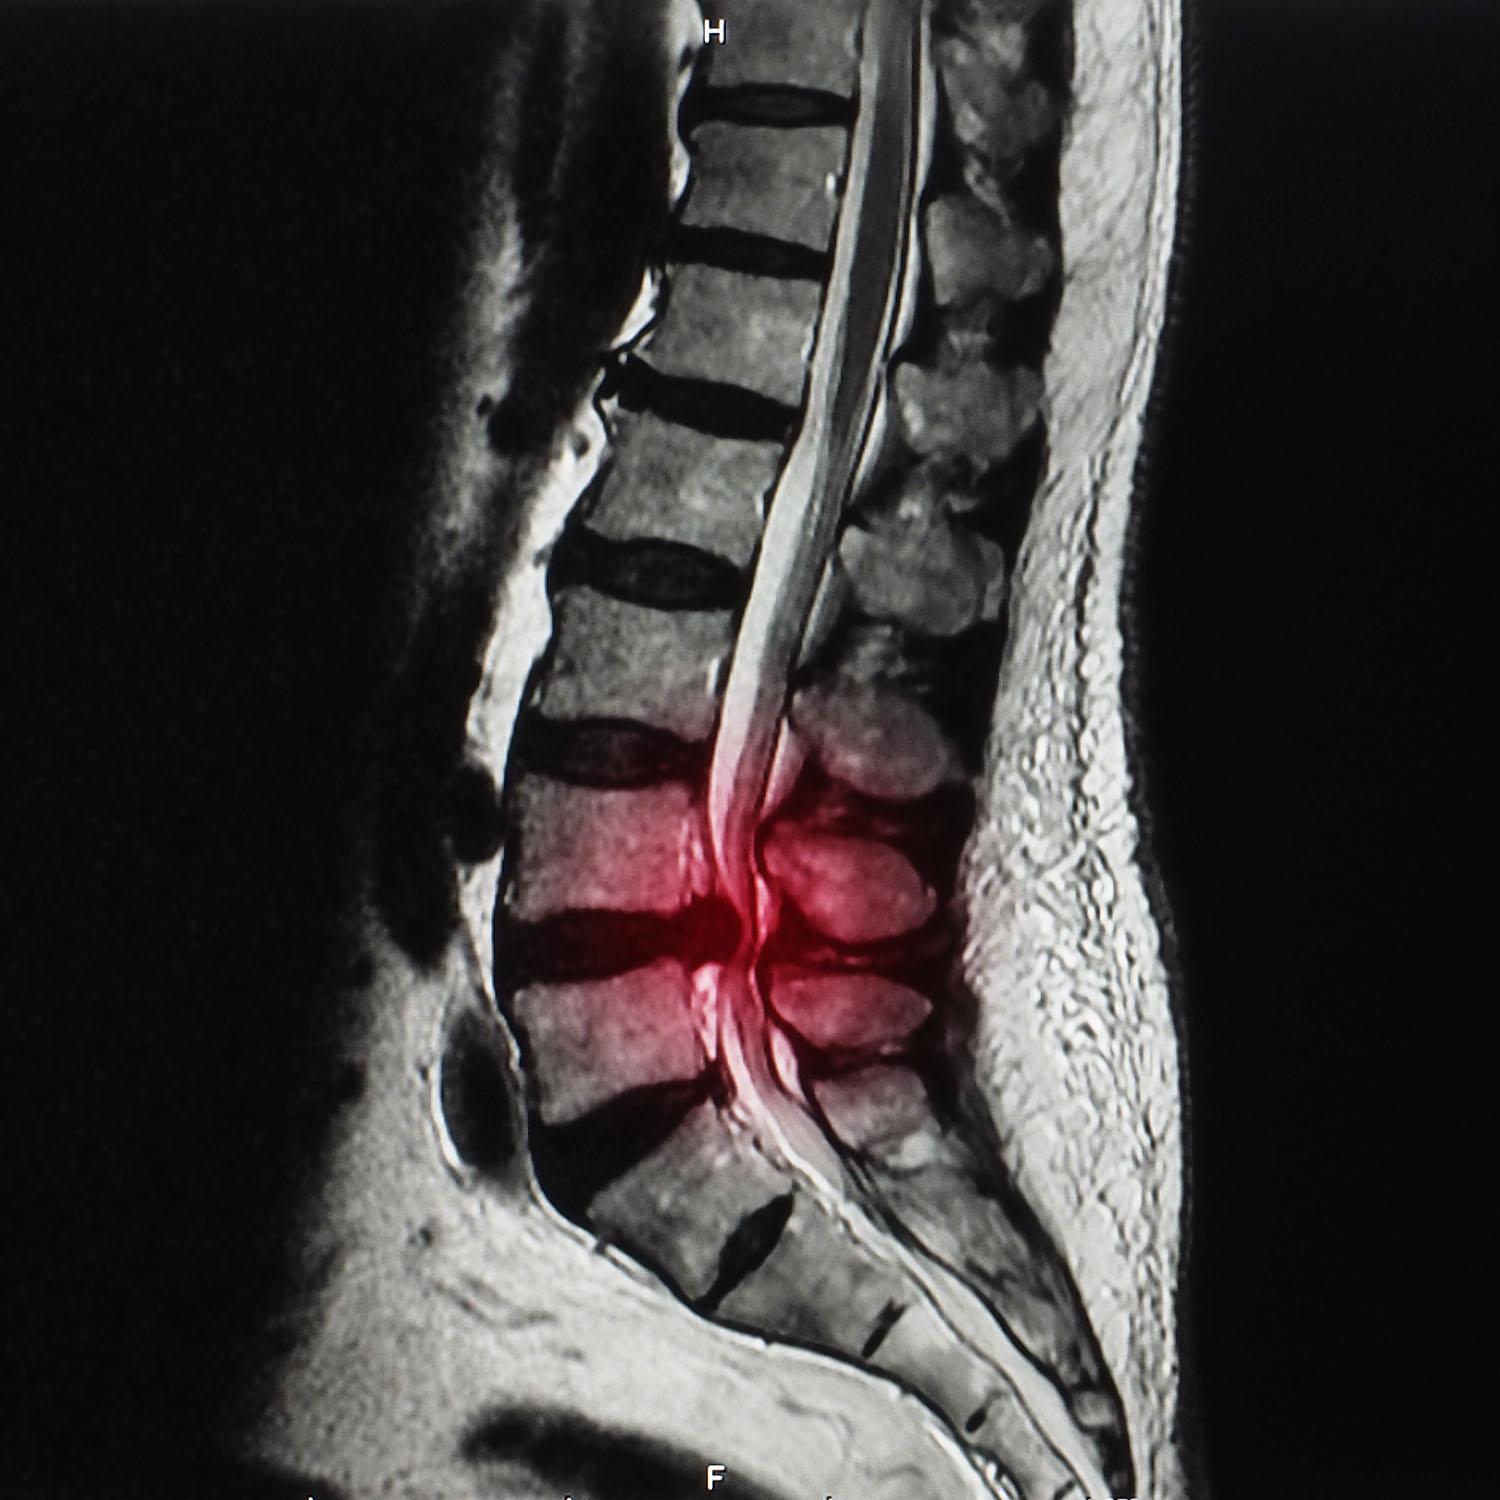

Cauda equina syndrome (CES) is caused by compression of the lumbosacral nerve roots that extend below the spinal cord. The most common cause is disc prolapse at the L4/5 or L5/S1 level and stenosis of the spinal canal. Less commonly, compression may be due to pathology in a higher disc or to a tumour, infection or trauma. Typical symptoms and signs of CES include leg and/or back pain, together with one or more of: bladder or bowel dysfunction; altered perianal, perineal or genital sensation; motor weakness affecting both legs; sexual dysfunction. It is a medical emergency and a missed diagnosis can have devastating consequences. In this episode, Dr Roger Henderson covers the anatomy and causes of CES, its presentation, diagnosis and treatment pathway.

- Magnetic resonance imaging is the imaging modality of choice, offering detailed views of soft tissue, nerve roots and spinal cord structures.